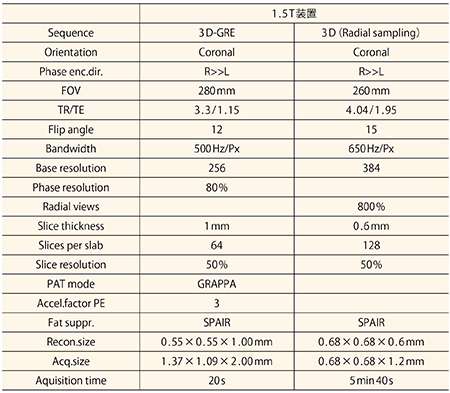

RVS用MRIは,コントラストが明瞭な画像を提供することが重要である。また,超音波診断装置では,MRIの画像はかなり拡大されて表示されるため,より高分解能画像の方がRVSの際には医師に貢献できると思われる。より高分解能なRVS用MRI画像取得のため,Radial sampling法を応用した3D-GREシーケンスを検討した。通常呼吸下でもモーションアーチファクトが大幅に低減された画像を取得することができるため,当院では腹部や骨盤部でも応用している。このシーケンスは,脂肪抑制は併用可能だが,パラレルイメージングを併用できないため撮像時間が長い(5min40s)が,ボクセルサイズはこれまでのシーケンスに比べて小さくすることができる。撮像条件・画像を示す(表3,図5)。Radial sampling法を応用した3D-GREシーケンスについては高評価をいただいている。現在,Radial sampling法で撮像する際には,造影剤は0.1mL/sで注入しているが,今後検討を加えていきたいと思っている。

表3 高分解能RVS用MRIの撮像条件